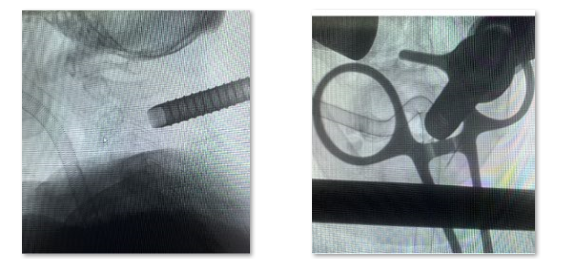

术中透视